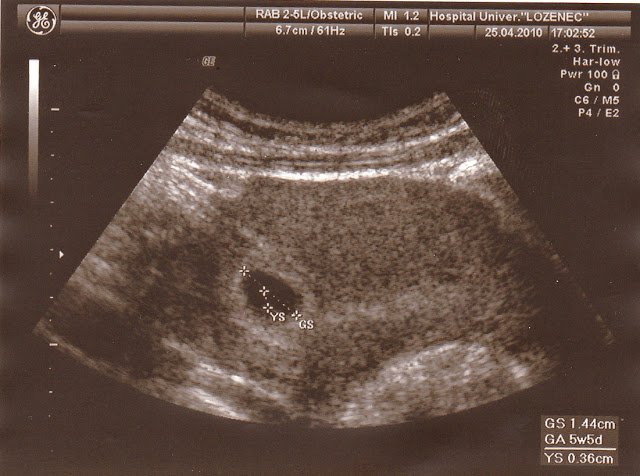

Момичета, ето и първата снимка на нашето второ детенце - по-скоро то не се вижда, но това му е къщичката Simple Smile  Heart Eyes

В петък повече:)